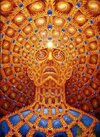

Самый мало изученный стафф, как известно LSD. Многие неискушённые задаются вопросом: как воздействует на восприятие и психику сей божественный оплот ныне почившего в бозе кумира психоидов и психонафтов Альберта Хоффмана?

Проводилась масса экспериментов и опытов, чтобы установить, как же именно прёт? Не обошлось тут конечно без самых страждущих: художников.

Самый мало изученный стафф, как известно LSD. Многие неискушённые задаются вопросом: как воздействует на восприятие и психику сей божественный оплот ныне почившего в бозе кумира психоидов и психонафтов Альберта Хоффмана?

Проводилась масса экспериментов и опытов, чтобы установить, как же именно прёт? Не обошлось тут конечно без самых страждущих: художников.